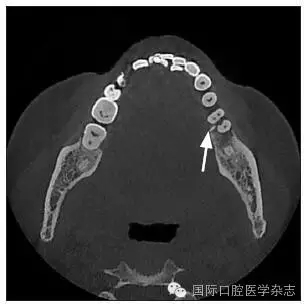

患者,女,42歲,因牙痛就診于中南大學(xué)湘雅醫(yī)學(xué)院附屬??卺t(yī)院牙體牙髓病科。臨床檢查為左側(cè)下頜第一磨牙遠(yuǎn)中齲,根尖壓痛和扣痛及頰側(cè)深牙周袋,牙髓電活力檢查陰性,近中根尖放射透明影。X線檢查根分叉區(qū)有不透明突起,扁形,

1.8 mm寬、8 mm長(zhǎng)(圖1~3)。

圖 2 CT水平面觀

Fig 2 CT horizontal section view